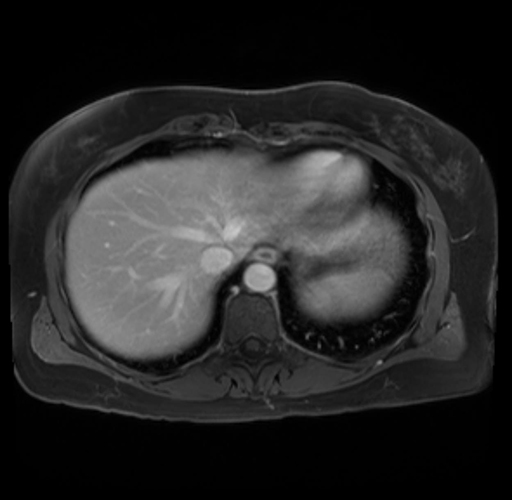

Imaging Analysis

Look through the patient's CT scan to identify any areas of concern for the necessary procedure.

Based on your CT findings, which issue(s) are present and would give reason for "planned slowing down moment(s)" in this case?

Considering a standard distal pancreatectomy procedure, what step(s) of the operation would you do differently in this case?